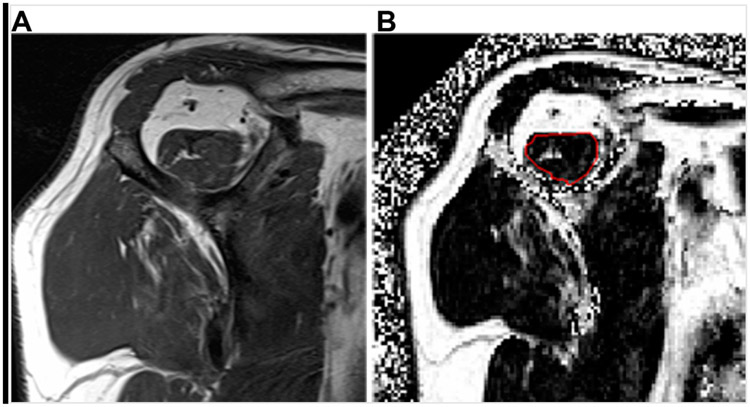

Abstract Image